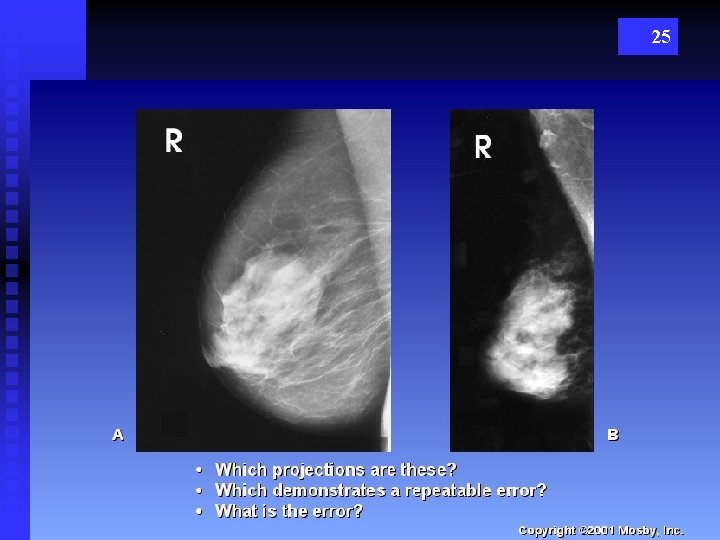

25